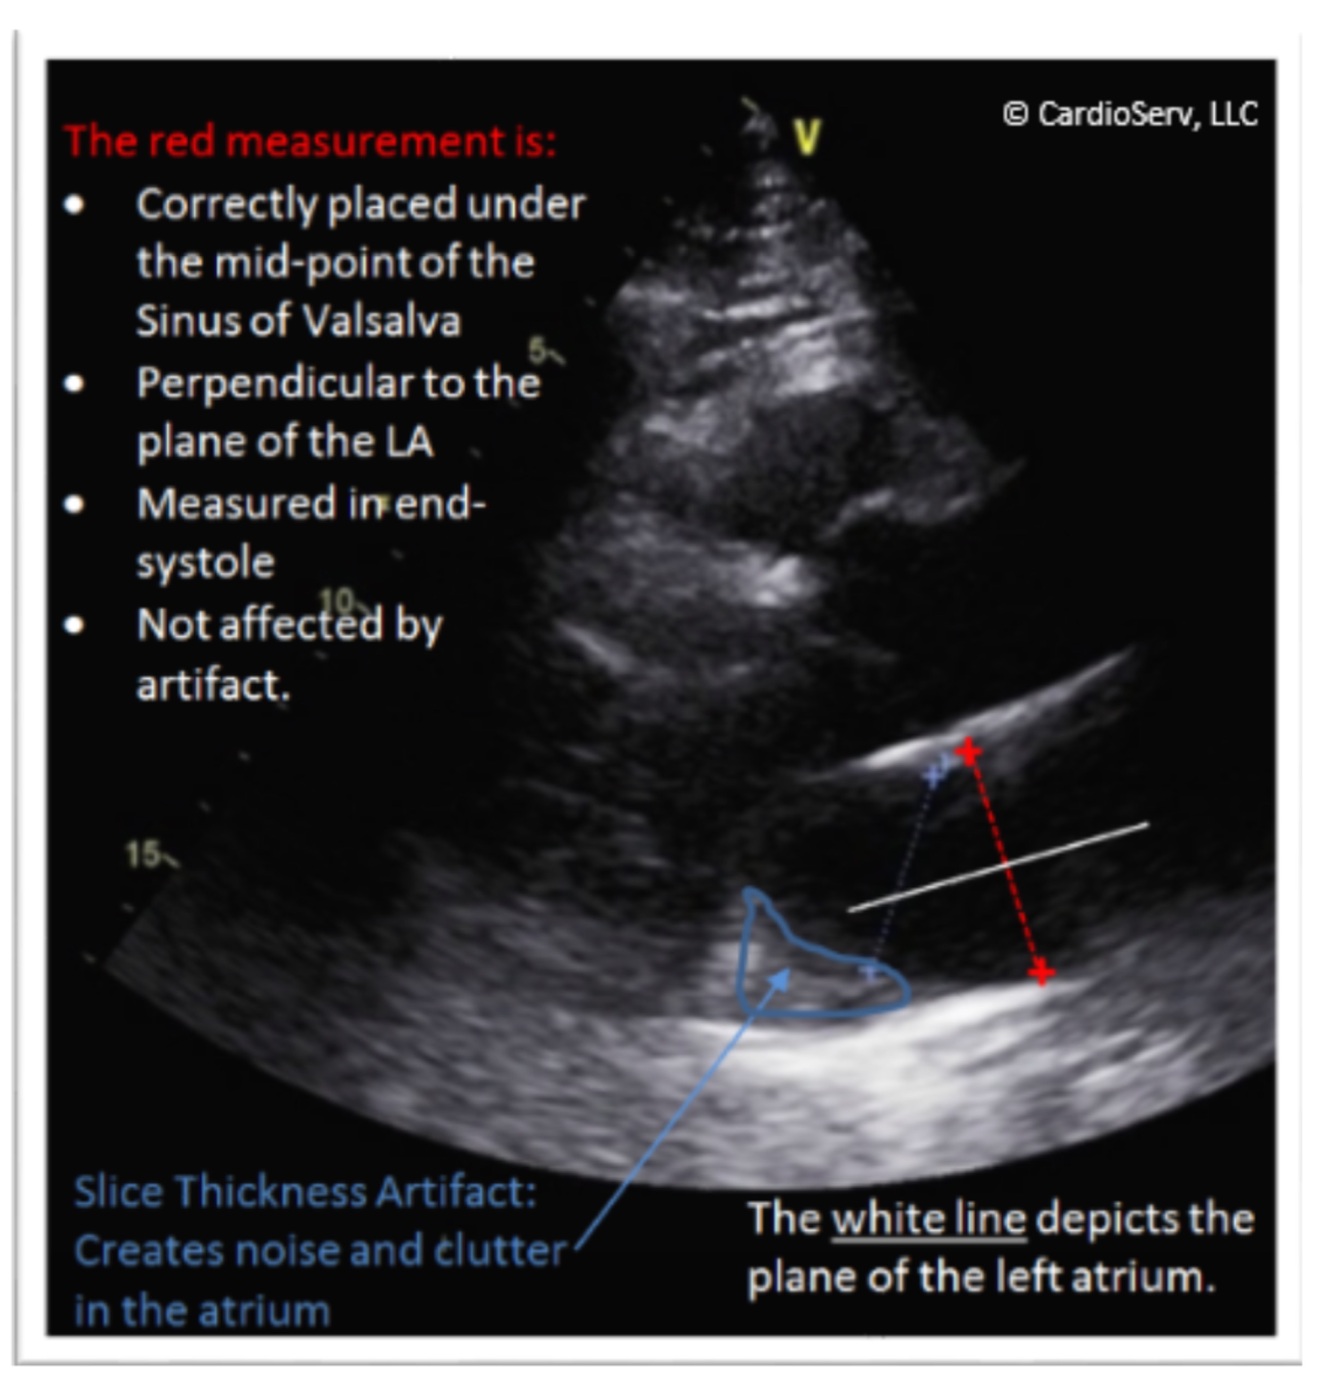

LA linear dimension

LA measurement

PLAX

When: end systole (atrium is largest)

Where: midpoint of sinus of valsalva

Measure perpendicular to annular plane, mid plane of mitral annulus to midpoint or superior wall, do not include LAA/PV